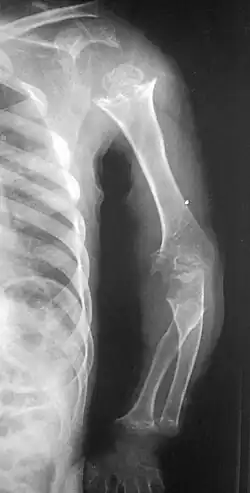

| Pseudoachondroplasia. Shoulder and humerus. Note the dysplastic proximal humeral epiphysis, metaphyseal broadening, irregularity and metaphyseal line of ossification. These changes are collectively known as "rachitic-like changes". Lesions are bilateral and symmetrical. | |

Skeletal radiography

Accurate assessment of plain radiographic findings remains an important contributor to diagnosis of pseudoachondroplasia. It is noteworthy that vertebral radiographic abnormalities tend to resolve over time. Epiphyseal abnormalities tend to run a progressive course. Patients usually suffer early-onset arthritis of hips and knees. Many unique skeletal radiographic abnormalities of patients with pseudoachondroplasia have been reported in the literature.[2][7][4]

- Dysplastic/hypoplastic epiphyses especially of shoulders and around the knees.

- Metaphyseal broadening, irregularity and metaphyseal line of ossification. These abnormalities that are typically encountered in proximal humerus and around the knees are collectively known as "rachitic-like changes".

- Radiographic lesions of the appendicular skeleton are typically bilateral and symmetric.